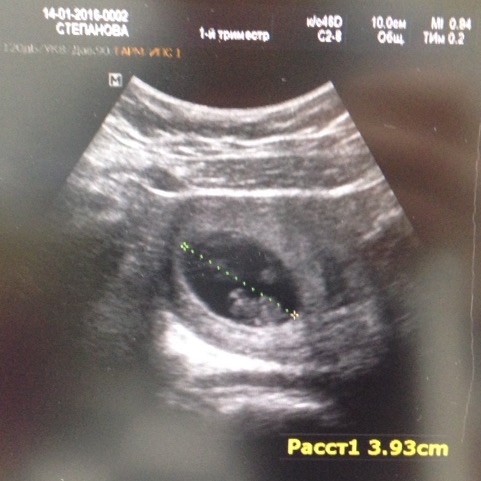

УЗИ, КТГ, доплерПаника-паника в голове!😰 3 дня СБ найти не могу!!! Дома не мерзла вчера, на обед на пополам (80% Нюся, 20%-я) стали вонючий бизнес ланч, и ничего! Грудь менее чувствительная стала. Ой-ойНочью то бабка снизу спать не давала-телек смотрит громко очень, потом в 7 собака соседская разбудила.😬😬😬😬 Спала плохо, встала злая и нервная, СБ опять не нашла. Кое-как позавтракали и рванули с Нюсей на узи через сугробы.

Нашли нас, все на месте. Тетя врач покрутила у виска и удивилась, зачем вообще все эти допплеры-лучше на узи чаще ходить-тут все точно расскажут и покажут. Ага, за 2 тр 😬

Вот такие мы уже большие - КТР 20 мм, что соответствует сроку 8-9 недель. Погуглив, получила более точную информацию: 8.6-нагоняем потихоньку!

ЧСС 152 уд/мин

Ручки уже видны, ножки 😍